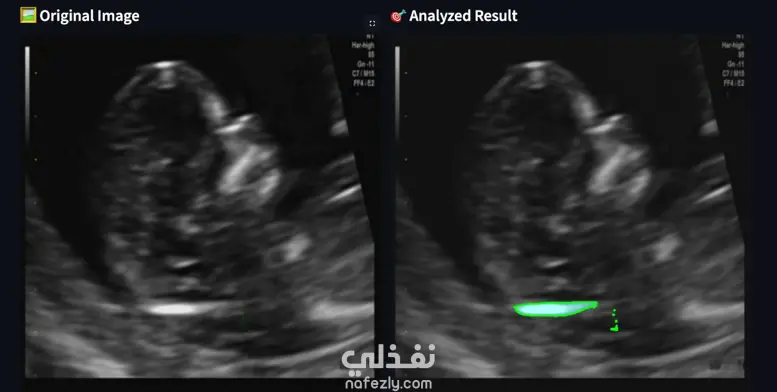

نظام متقدم للرؤية الحاسوبية لاكتشاف العلامات المبكرة للتطور العصبي من الأشعة الطبية. يغطي المشروع كامل سلسلة العمل من البداية للنهاية: بدءًا من معالجة البيانات الأولية، مرورًا بـ استخراج الخصائص وتدريب النماذج، وصولًا إلى الاستدلال المعاير لتقديم توقعات دقيقة وموثوقة. باستخدام تقنيات التعلم العميق المتقدمة، يوفر النظام نتائج سريعة ودقيقة وقابلة للتفسير، مما يمكّن الأطباء من التعرف على العلامات الحرجة مبكرًا وتحسين نتائج المرضى.